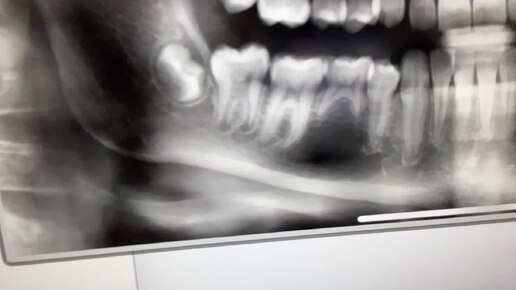

Ретенированные зубы. Разбор клинического случая, обоснование выбора тактики лечения.